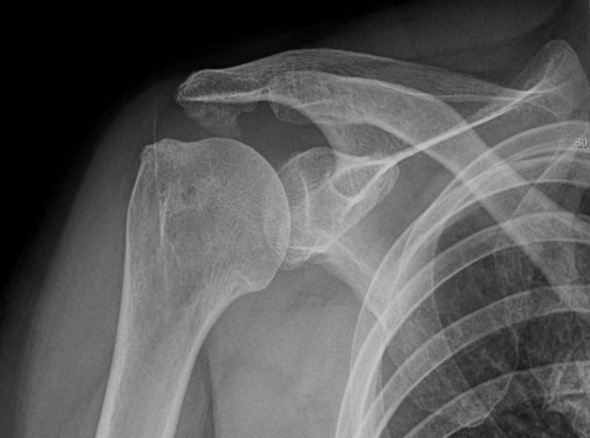

보존적 치료에 호전되지 않는 경우

회전근개 파열로 진행되고 있는 경우

극심한 통증을 동반하고 있는 경우

이러한 경우

내시경 시술을

고려합니다.